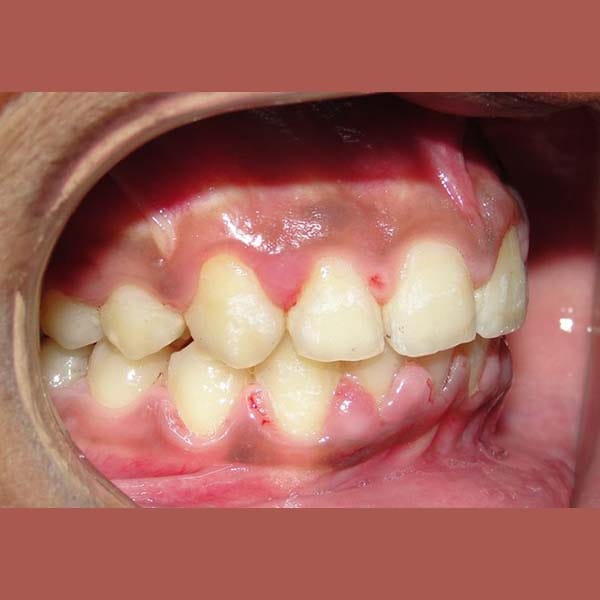

عانى هذا الشاب اليافع من بروز شديد في الأسنان وصل إلى 1 سم، وكان سببه الرئيسي هو تراجع الفك السفلي، وهو ما كان يظهر بوضوح على بروفيل وجهه الجانبي.

تم العلاج على مرحلتين لاستغلال فترة النمو:

كما تظهر الصور، كان التحسن جذرياً ليس فقط في الابتسامة ولكن في تناسق ملامح الوجه بالكامل. تم تصحيح البروز، وتحسنت علاقة الفكين، وحصل الشاب على ابتسامة جميلة وواثقة.